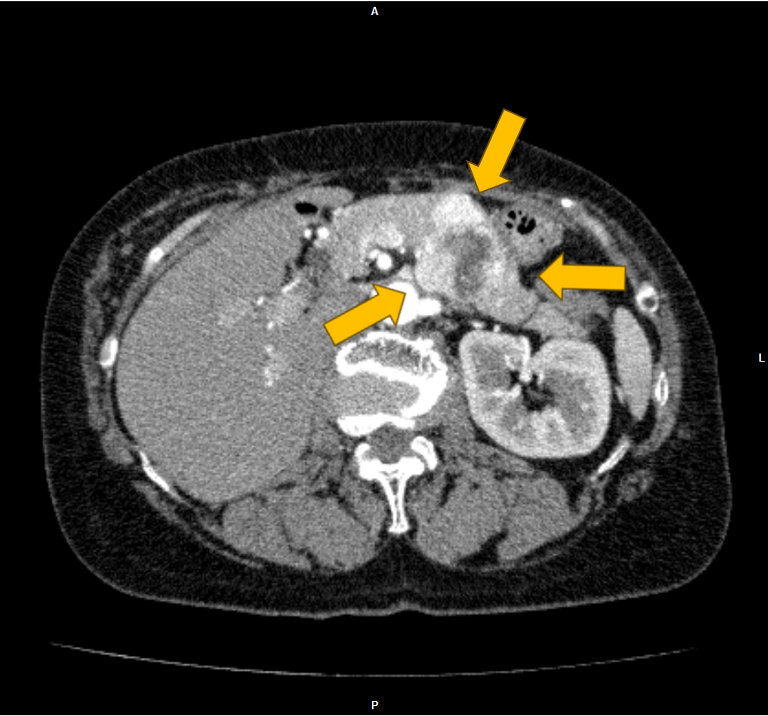

右腎癌(淡明細胞型腎細胞癌)術後の経過観察中に、左腎、膵尾部、胸骨の腫瘍が明らかとなり、胸骨病変の組織診断により右腎癌の転移の確定診断となった。本CTは化学療法中の治療効果判定目的に施行された腎ダイナミック造影CTである。

当該疾患の診断における造影CTの役割

右腎癌術後(淡明細胞型腎細胞癌)、左腎、膵体部、胸骨背側に腫瘤を認める。造影CTにおいての膵実質との増強効果の違いにより膵腫瘍を描出することができる。膵腫瘤はDynamic造影で早期濃染色、washoutパターンを呈しており、乏血性の造影パターンを呈す通常の膵癌との鑑別は容易である。